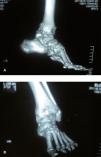

Al examen físico se encontró a una paciente eutrófica, con marcha antálgica; en la inspección del tobillo izquierdo, se observó edema en la región del maléolo lateral, con deformidad en varo de tobillo y retropié, limitación de los arcos de movimiento del tobillo, con flexión de 20° y extensión de 10°; en la articulación subtalar había crepitaciones e intenso dolor con los movimientos (figura 1).

Al examen radiográfico del tobillo afectado, se encontraron importantes cambios artrósicos y deformidad de las articulaciones tibiotalar y subtalar; la proyección anteroposterior mostraba deformidad en varo de 40° con desplazamiento talar y ángulo talocrural de 170°.

En la tomografía se apreciaba la gran deformidad de la artrosis con osteofitos en la articulación tibiotalar y subtalar (figura 2).